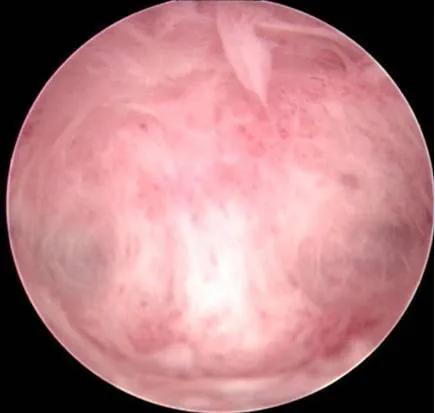

子宫内膜息肉